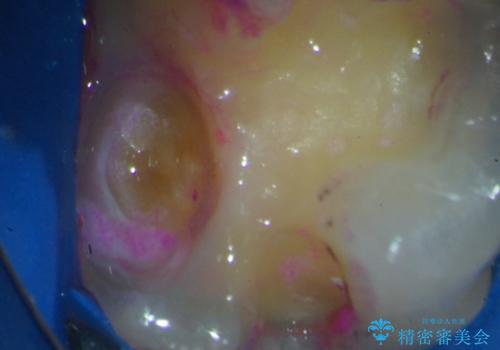

歯髄方向 歯肉方向へと深い 2種類の大きな虫歯

#17は失活歯で歯肉方向への縁下カリエス、#16は生活歯であるものの歯髄ギリギリの処置となるであろうとが予想される治療です。

歯周外科、マイクロスコープを用いた虫歯治療を行い歯を残す治療計画を立てます。